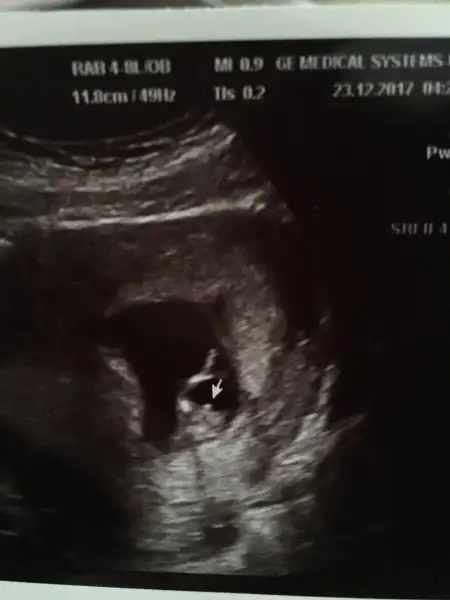

Kızlar merhaba.Ultrason resimlerinden cinsiyet tahmini yapabilen var mı aranızda? Bir sürü teoriler var iyice kafam karıştı. Aslında öğrenmenin önemi yok da insan merak ediyor işte ☺️

12 haftada dogru ve guzel resimle nuba bakilir ona göre tahmin yapilir